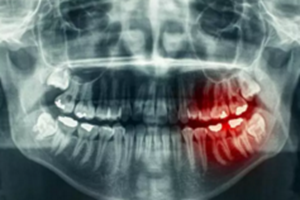

牙齒長(zhǎng)在牙槽骨里,形態(tài)變化多端,所需要的手術(shù)時(shí)間及手術(shù)風(fēng)險(xiǎn)也有差別,所以醫(yī)生會(huì)要求拔牙前給你進(jìn)行X線牙片檢查,遇到疑難病例還要進(jìn)行牙科三維CT檢查。

為什么有些牙齒不能拔?拔牙無(wú)小事!

這些檢查手段可以讓醫(yī)生知道你牙根的長(zhǎng)短、大小、數(shù)量、走向、彎曲程度、與周圍重要結(jié)構(gòu)的關(guān)系等等。只有明確拔牙方法,并評(píng)估拔牙風(fēng)險(xiǎn),才能使你這顆牙拔得更順暢。